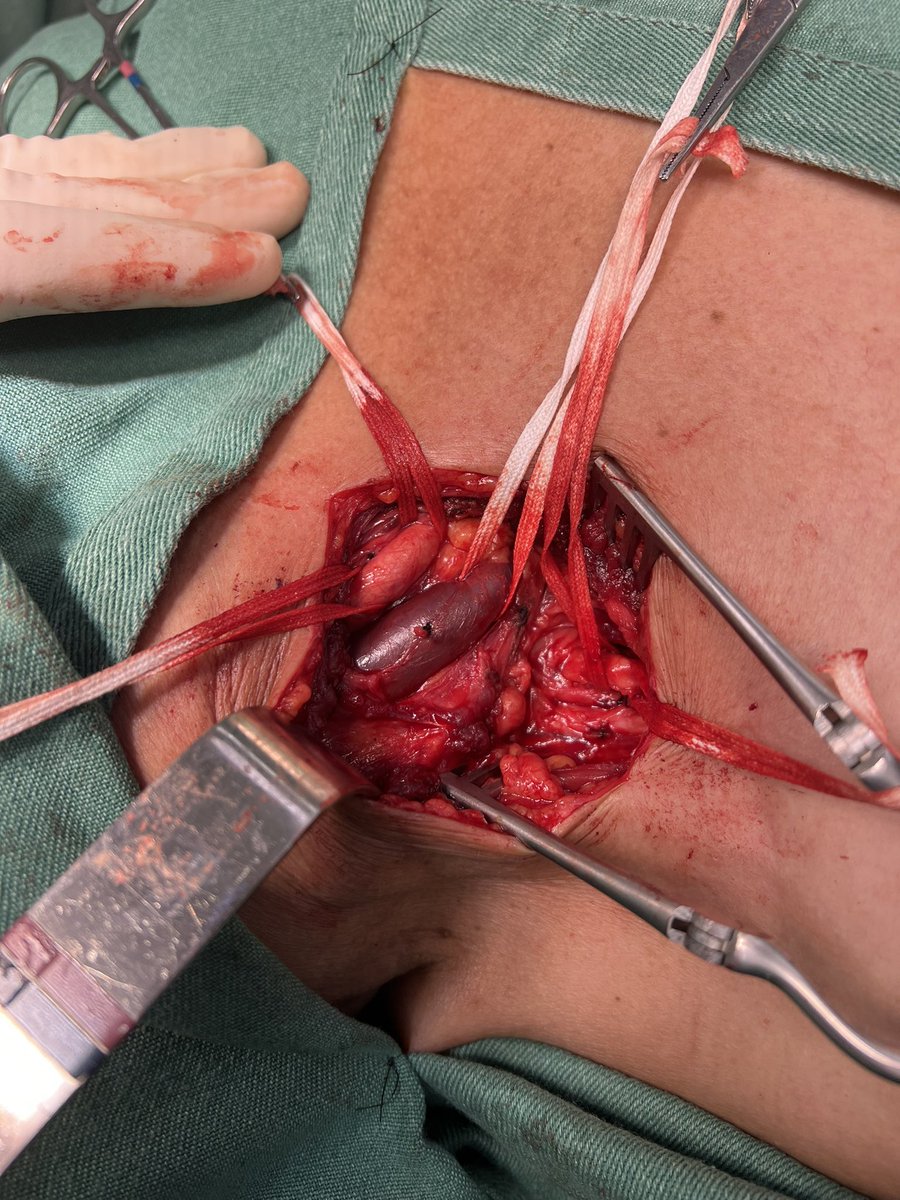

70 y, male, symptomatic splenic artery aneurysm. Open surgery, uneventful. Minimal bleeding. #vascularsurgery #oldfashionsurgery #tothebucket #aneurysm

@farkomd In fact, embolization would be my first option, but the patient had abdominal pain, and the public system did not have coils available in the hospital. We ended up doing the best with the resources we had.

This is a spleen attached to a splenic artery aneurysm. Treatment could’ve been done with coils leaving the spleen in the body, the aneurysm excluded and a major operation avoided IMHO